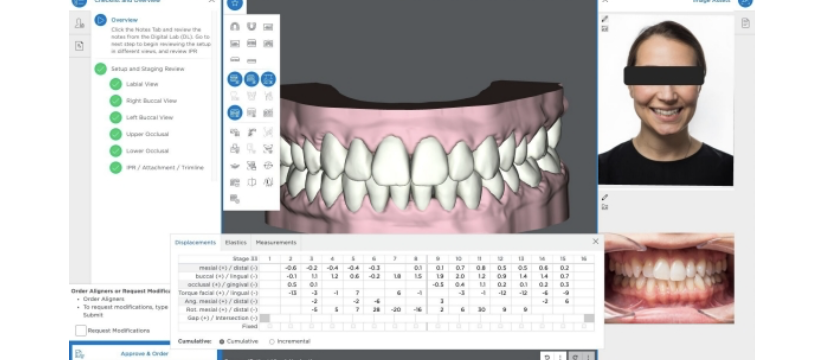

Shape Memory Aligner : 60's Non Extraction Anterior Crowding and Deepbite. Totally zero attachment Approach 形状記憶アライナー矯正装置 60代女性非抜歯 過蓋咬合 前歯部叢生, アタッチメント装着無し Shape Memory Aligner : Non Extraction Anterior Crowding

Shape Memory Aligner : 60's Non Extraction Anterior Crowding and Deepbite. Totally zero attachment Approach 形状記憶アライナー矯正装置 60代女性非抜歯 過蓋咬合 前歯部叢生, アタッチメント装着無し Shape Memory Aligner : Non Extraction Anterior Crowding

Shape Memory Aligner : 60's Non Extraction Anterior Crowding and Deepbite. Totally zero attachment Approach 形状記憶アライナー矯正装置 60代女性非抜歯 過蓋咬合 前歯部叢生, アタッチメント装着無し Shape Memory Aligner : Non Extraction Anterior Crowding ,

Shape Memory Aligner : 60's Non Extraction Anterior Crowding and Deepbite. Totally zero attachment Approach 形状記憶アライナー矯正装置 60代女性非抜歯 過蓋咬合 前歯部叢生, アタッチメント装着無し Shape Memory Aligner : Non Extraction Anterior Crowding , アライナー矯正装置 バイブレーションディバイス | ソフィア歯列矯正歯科医院,